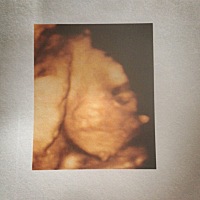

二宝18天了❤️